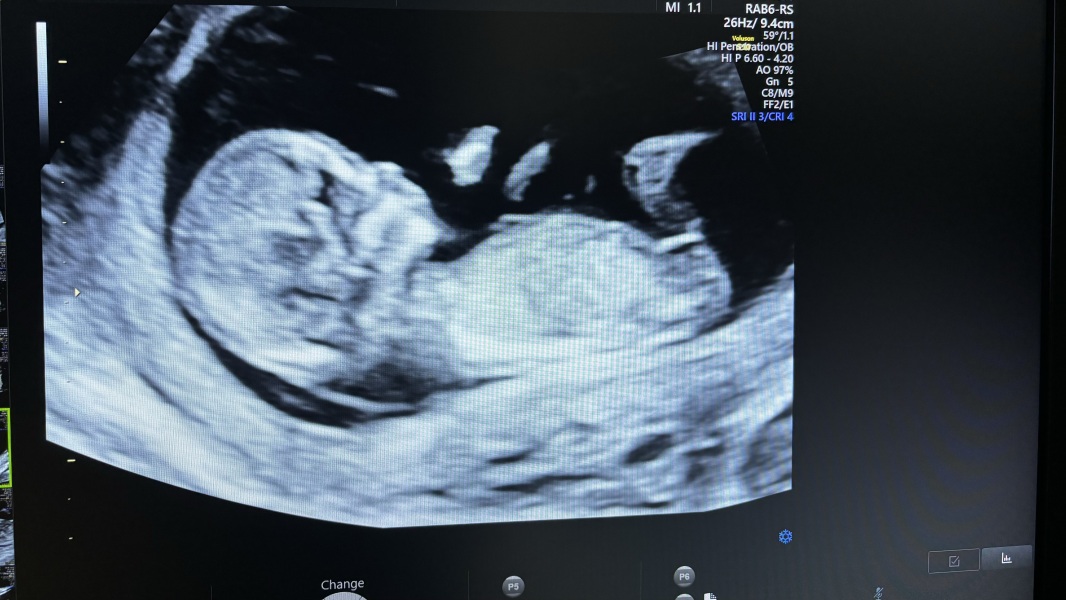

Hi everyone, I have been a bit MIA as not been doing too well mentally and physically. I had my 12 week scan today and went in as 12+4 only to come out as 13+3 based on baby’s length which is a whole week off. Relieved that they said everything looks healthy and that baby is doing well for its gestation. Still struggling on and off with nausea but my ptyalism is really getting me down as making it impossible for me to be in any social situations.

A little photo scan of the baby with a very visible nub, doctor took a guess and said girl.

That’s a great picture @Daydreamer94 congratulations 😊 we got bumped up a couple of days too, I went into the appointment as 12+4 and came out as exactly 13 weeks 😊

Gosh that is an extremely girly scan looking at nub and round head 🥰

@Daydreamer94 looks very similar to my baby's scan and the nub queens on Facebook said girl for me!